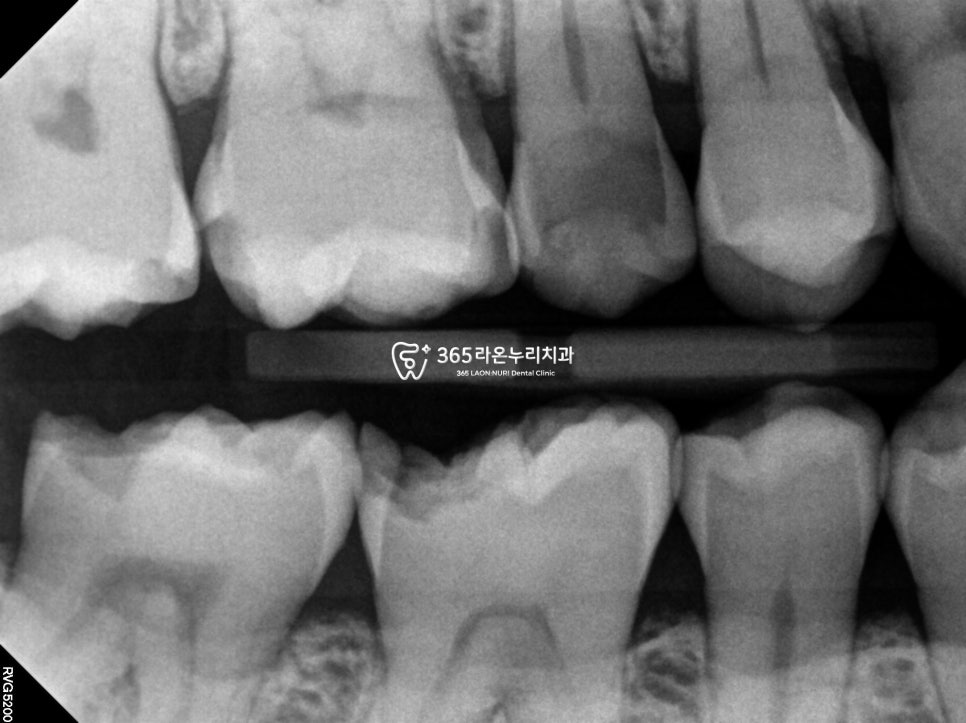

2025. 04. 30

오늘 신장동 치과 에서

설명드리는 치료부위 치근단

사진을 봤을 때

다행히 신경까지 손상이 없었고,

구강스캐너를 통한

원데이 오버레이 치료 과정을

보겠습니다.